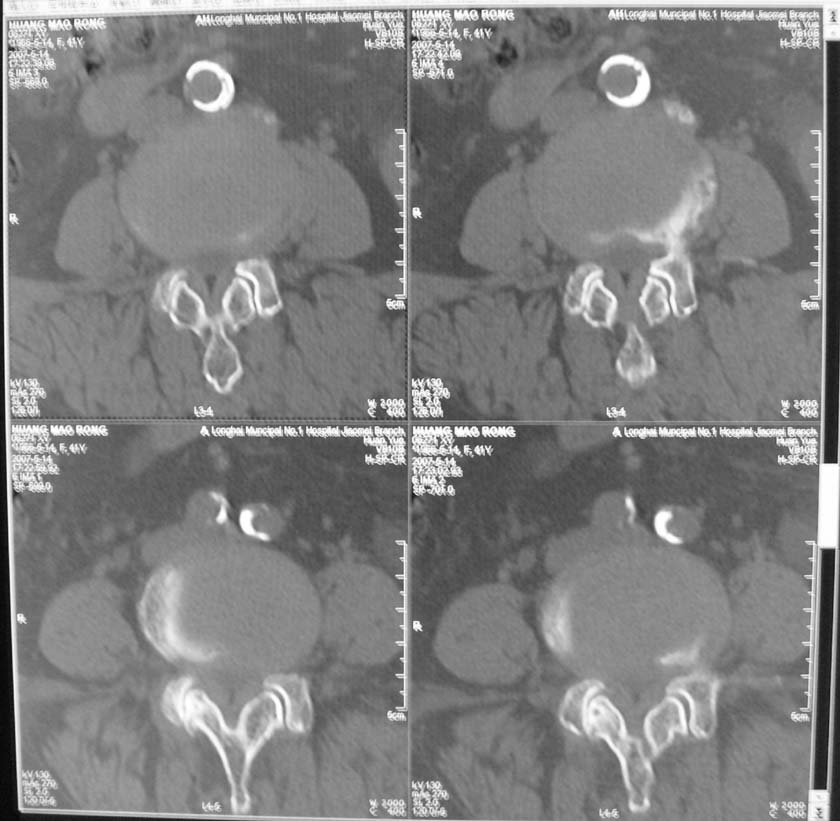

以下是引用jiangjing在2007-5-16 11:05:00的发言:[br]zhichi [br]ct所见:[br]l4-5椎间盘膨出,双侧黄韧带增厚,致使对应椎管变窄,硬膜囊受压.[br][br]l5-s1椎间盘后突,其后硬膜囊受压.l3-4椎间盘未见突出征象.[br]诸椎体边缘及对应椎小关节突骨质增生.腰椎生理曲度正常.[br]腹主动脉壁广泛钙化.[br]印象:[br]1、l4-5椎间盘膨出并双侧黄韧带肥厚及椎管狭窄。[br]2、l5-s1椎间盘突出。[br]3、腰椎及椎小关节退变。